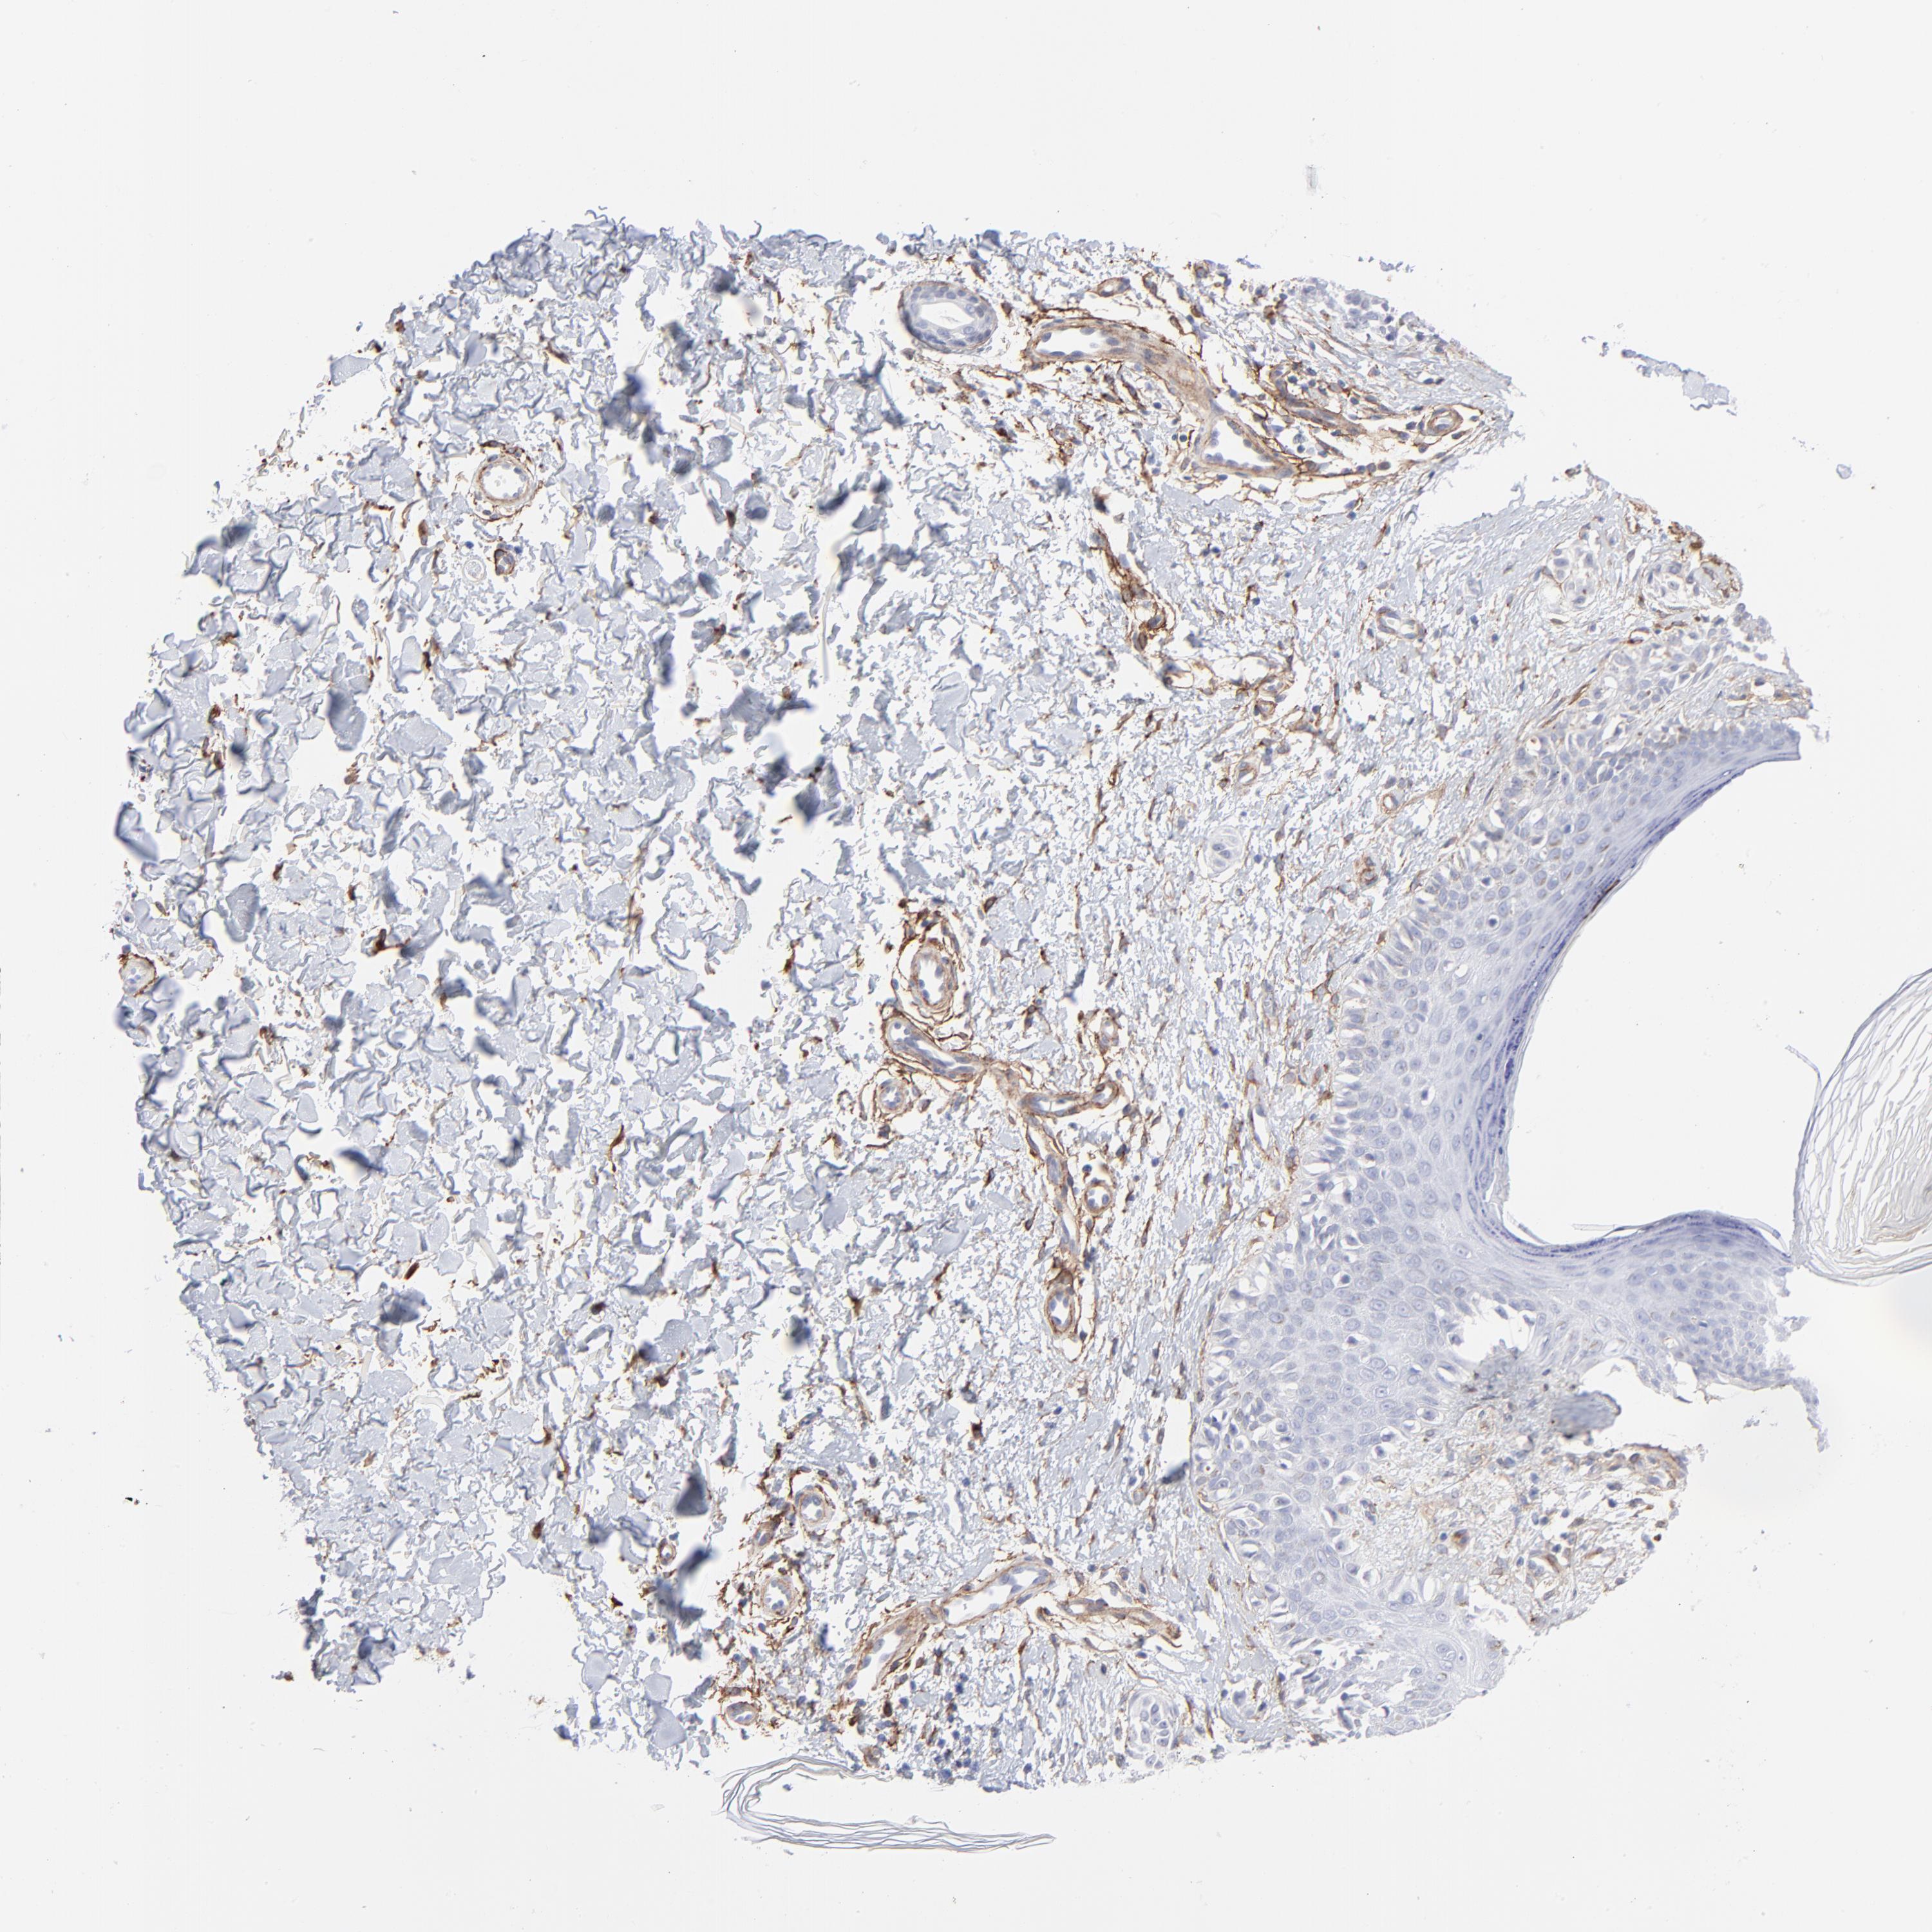

MELANOMA - Protein expressioni

A mouse-over function shows sample information and annotation data. Click on an image to view it in a full screen mode. Samples can be filtered based on level of antibody staining by selecting one or several of the following categories: high, medium, low and not detected. The assay and annotation is described here.

Note that samples used for immunohistochemistry by the Human Protein Atlas do not correspond to samples in the TCGA dataset.

Antibody stainingi

Antibody staining in the annotated cell types in the current human tissue is reported as not detected, low, medium, or high, based on conventional immunohistochemistry profiling in selected tissues. This score is based on the combination of the staining intensity and fraction of stained cells.

Each image is clickable and will lead to virtual microscopy that enables deeper exploration of all samples and also displays staining intensity scores, fraction scores and subcellular localization as well as patient and tissue information for each sample.

Antibody CAB003842

Antibody CAB018144

Staining

High

Medium

Low

Not detected

Intensity

Strong

Moderate

Weak

Negative

Quantity

>75%

75%-25%

<25%

None

Location

Nuclear

Cytoplasmic/membranous

Cytoplasmic/membranous,nuclear

Malignant melanoma, NOS

Malignant melanoma, Metastatic site